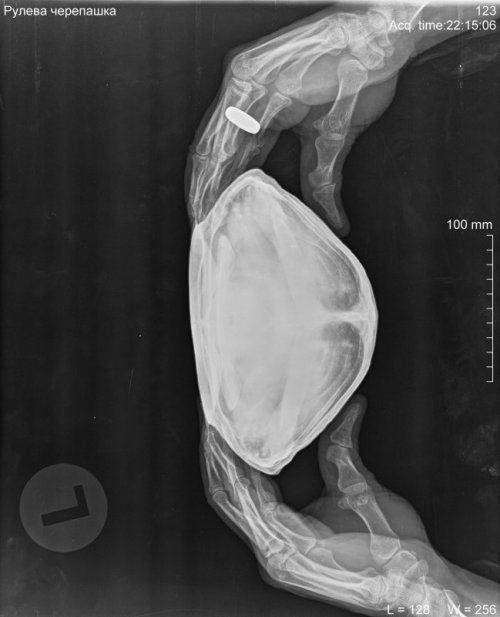

Podolnyi Ваше имя: Подольный Константин Локация: Украина, Днепр Опубликовано: 2 февраля 2020 Опубликовано: 2 февраля 2020 На рентгене просматриваются 3 контрастных конкремента, но мне не нравится характер их расположения. Нужно делать узд черепахи, через паховую ямку, для исключения фолликулярного стаза. Ибо на рентгене, как по мне, я вижу фолликулы на разных стадиях созревания. С большей долей вероятности, это петрификация(кальцинация) фолликулов. С правой стороны (возле таза) виден контрастный участок, я предполагаю это в устье яйцевода. Через клоаку пальпировали черепаху?

Podolnyi Ваше имя: Подольный Константин Локация: Украина, Днепр Опубликовано: 7 февраля 2020 Опубликовано: 7 февраля 2020 К примеру почему нужно очно смотреть такого рода проблемы. На фото представлен рентген черепахи и справой стороны компьютерная томография. На рентген видно, но крайне плохо, на кт, сами видите